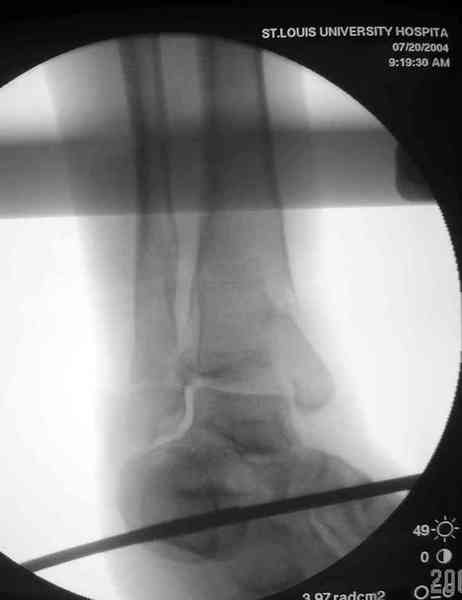

Яков изложил все необходимые аспекты лечения переломов пилона, и, не желая менять тему, решил выставить нашу точку зрения в двух клинических примерах.

При лечении внутрисуставных переломов типа "Pilon"

или "Tibial Plateau" на голени, применение простых

наружных фиксаторов типа "Spanning ExFix" или "Travelling ExFix" стал одним из стандартом этапного лечения.

Здесь выставлена пара случаев перелома пилона, оба

случая леченные этапным наружным фиксатором.